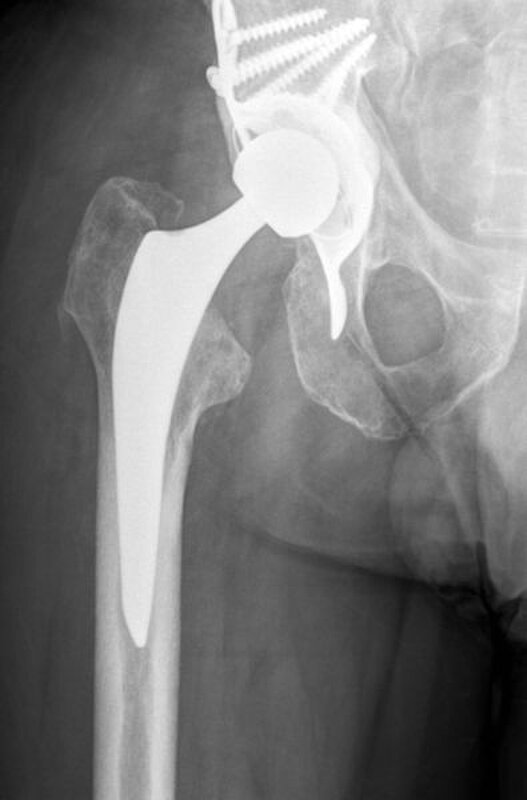

Procedere: Nach der entsprechenden Vorbereitung erfolgte im September der Ausbau der McMinn-Prothese sowie die Resektion des Schenkelhalses, ein Débridement im Bereich des Hüftgelenkes sowie die Einlage eines Spacers (i.S. einer Copal Zementeinlage) in die Hüftpfanne und im Bereich des proximalen Femurschaftes (Girdlestone Situation). Ende November 2017 erfolgte 6 Wochen nach Spacer Implantation (Abbildung 2) eine erneute Wiedervorstellung zur Punktion des Hüftgelenkes als Vorbereitung auf den Prothesenwiedereinbau. Hierbei wurde erneut ein E. coli detektiert und eine antibiogrammgerechte Antibiose mittels Ciprofloxacin 500mg 1-0-1 fortgesetzte. Die Indikation zum Spacerwechsel wurde gestellt. Der Eingriff konnte geplant Anfang Dezember durchgeführt werden.

Ende Dezember erfolgte die erste Punktion des Hüftgelenkes, bei der schließlich kein Keimnachweis erfolgte. Nach 6 weiteren Wochen konnte ebenfalls kein Keim mehr im Hüftgelenk nachgewiesen werden, so dass für März 2018 der Hüft-TEP-Wiedereinbau geplant wurde. Bei der Vorbereitung und Planung (CT Diagnostik) zeigte sich ein relativ großer knöcherner Defekt im Bereich des kranialen Acetabelums, sodass mit einem Burch-Schneider- Ring (Abbildung 3) geplant wurde.